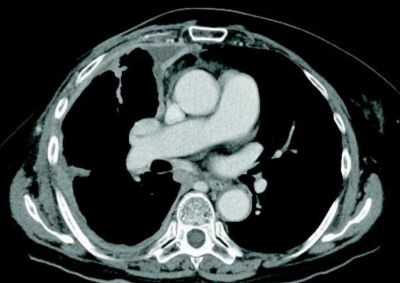

65 歳の女性。胸痛を主訴に来院した。1か月前から右胸痛を自覚していたが改善しないため受診した。13 年前に右乳癌で手術の既往がある。30 年前から建設業に従事していた。呼吸音は右下胸部で減弱、胸部の打診で右背側に濁音を認めた。

胸部エックス線写真、胸部造影CT及びFDG-PET/CTを別に示す。胸腔鏡下生検を施行した結果、カルレチニン免疫組織染色が陽性である悪性細胞を認めた。